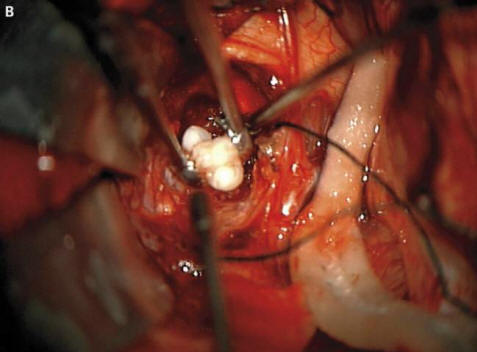

Kirurgi iz ameriške zvezne države Maryland so ga morali preživeti najtežjih operacij v svoji praksi. Štirimesečni starši fantje so sprožili alarm in po njem odšli k zdravnikom opazili, da glava njihovega otroka prehitro raste. Zdravniki opravili pregled in ugotovili, da je zob zrasel v bolnikovih možganih.

Fotografija iz odprtih virov Kot so razlagali kirurgi prestrašenim staršem in onkologi so bili to posledica nastanka redkega prirojenega tumorjev – kraniofariniomov, piše New England Journal of Medicine. Ta neoplazma v veliki večini primerov benigna pa lahko zraste do velikosti kroglice za golf in povzroča zmanjšanje vonja, poslabšanje sluha in vida ter povečuje tudi intrakranialni tlak. Raziskovalci vedno sumili, da se ti tumorji, ki se pojavijo pri otroku že prej nosečnost, ki nastane iz istih celic kot zob, saj so zaznali velike kopičenja kalcija, vendar pravi oblikovan zob, preden tega primera ne najdejo obračunano.

Kirurgi so fotografijo uspešno odstranili iz odprtih virov. Tumor oz. fant, so rekli, gre dobro. Vendar zob, ki odraščal v njegovi hipofizi, vendar je motil zlasti možgane, pravilna proizvodnja hormonov – bolnik jih bo moral vzeti prej konec življenja. Ta primer lahko upravičeno prevzame svoje mesto seznam najčudnejših operacij, ki jih opravijo onkologi. Medtem pa v mladenič iz Irana, ki je moral zdravite poraščene oči. Skoraj se je pojavil čuden tumor v očesu takoj po rojstvu, vendar se je pri 19 letih znatno povečala v velikosti (do 0,6 cm) in poleg tega preprečili zapiranje vek strogi lasje so začeli rasti. Zdravniki so tumor odstranili in to ugotovili gre za limbalni dermoid – navadno izjemno redko benigna vzgoja. Po mnenju zdravnikov bi v tem primeru dr. če bi mladenič še naprej vlekel z zdravili, je njegova oteklina ni mogel samo rasti las, ampak tudi začeti znojiti: sčasoma na novotvorbah se pogosto pojavijo ustrezne žleze.